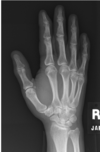

What type of joint is T?

C - Diarthrotic joint

The radiograph is a PA projection of the hand and wrist; an oblique projection of the thumb is obtained. The letter T is pointing out the first carpometacarpal joint, formed by the base of the first metacarpal and the trapezium. This is classified as a saddle type diarthrotic joint. Diarthrotic joints are freely movable joints and the most plentiful type of joint in the human body. Amphiarthrotic joints are partially movable; synarthrotic joints are immovable.